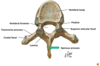

Vertebrae

How many vertebrae in each of the 5 vertebral column?

Cervical - 7

Thoraxic - 12

Lumbar - 5

Sacral - 1 (5 fused)

Coccyx (3-4 fused)